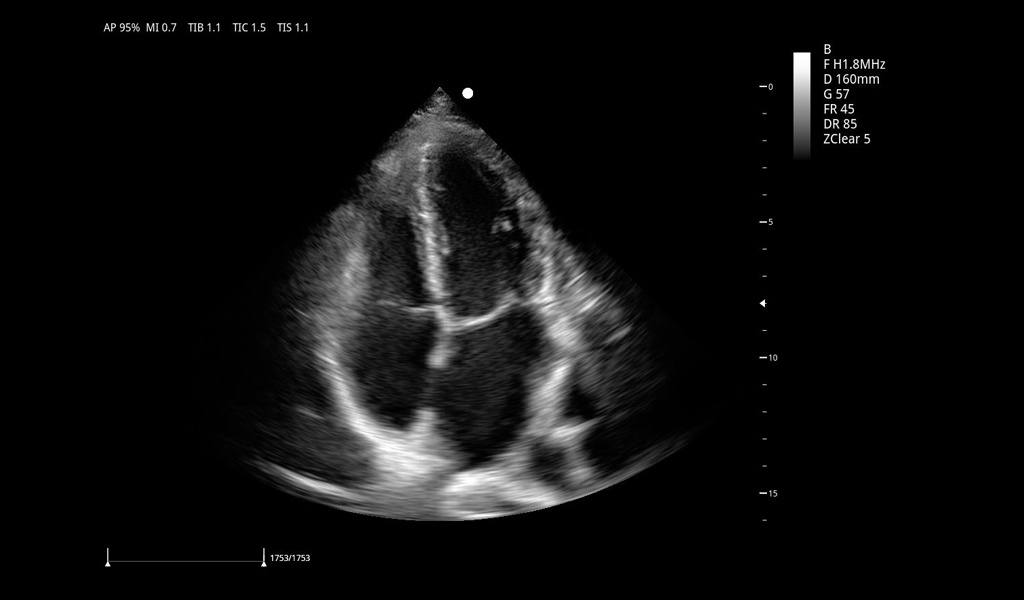

Excelentes imágenes clínicas

|

|

|

|

|

|